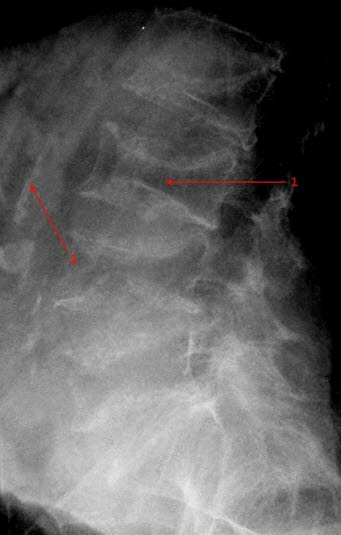

Osteoporose lumbalcolumna

Betydelig redusert kalktetthet og kompresjoner i alle lumbale virvler.

Bifunn: Veggforkalkninger i aorta

- Sammenfalt L3

- Kalk i aortaveggen